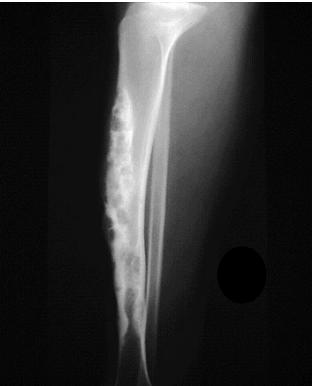

Resection & Reconstruction